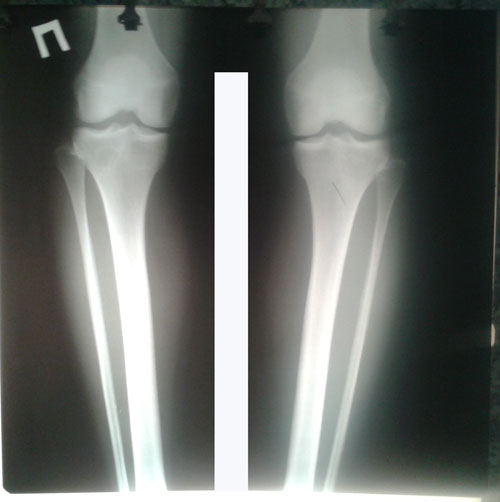

РЕНТГЕН ДО ОПЕРАЦИИ

Дата операции 14.07.2017г.

Дата снятия аппаратов 25.09.2017г.

Срок лечения 70 дней.